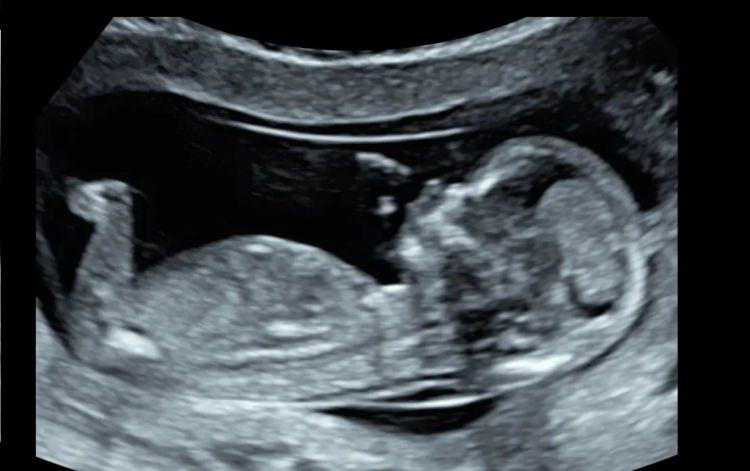

Anne adayı testleri kabul etmedi: Doktoruna 77 milyon tazminat cezası verildi!

Doktor aynı soruyu 14. ve17. hafta kontrollerinde de yineleyerek sordu. Ama anne adayı yine aynı cevapla testlerin yapılmasını kabul etmedi.